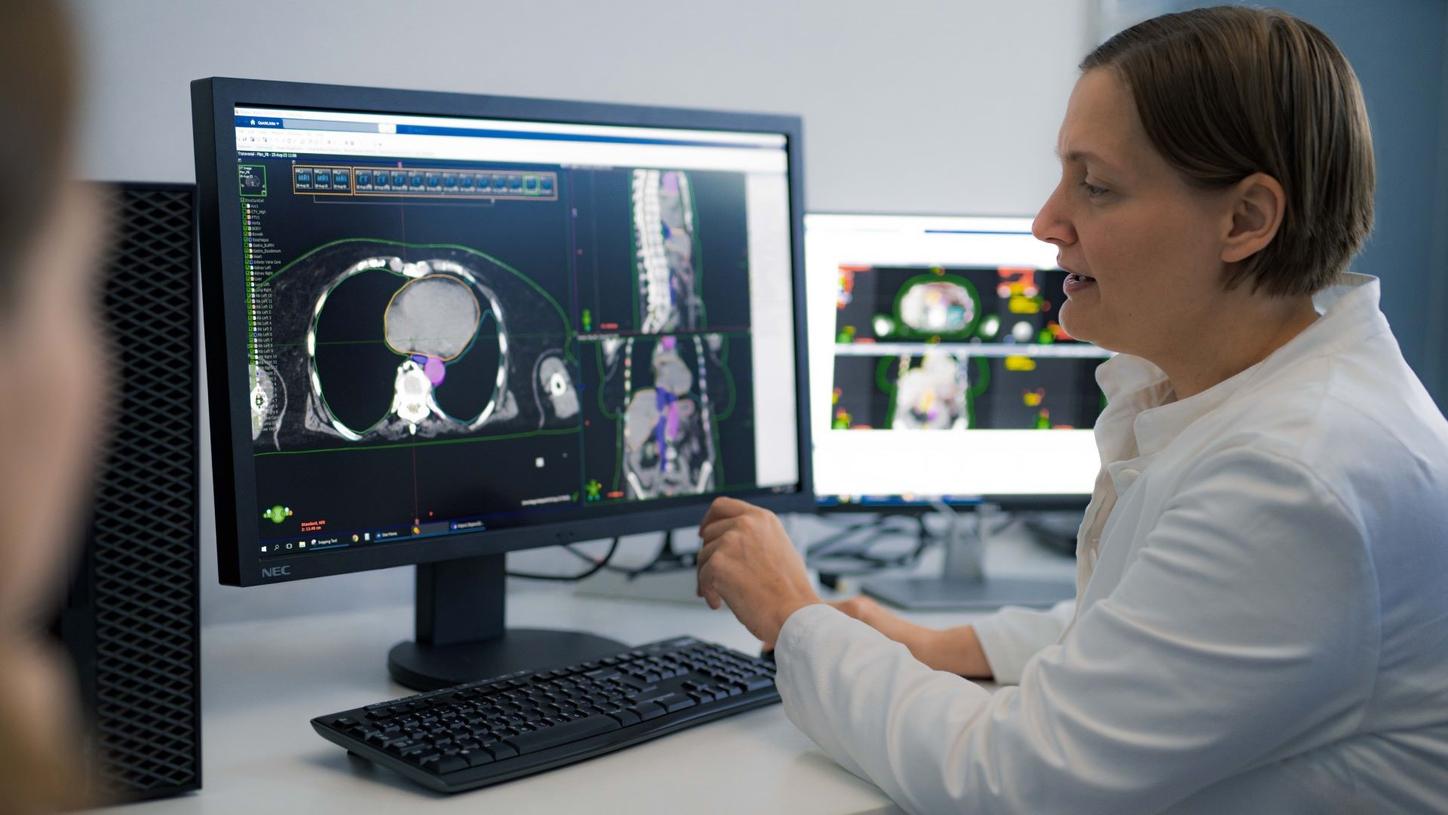

Our mission has evolved beyond merely developing new medical devices to delivering end-to-end, intelligent solutions to better support our customers. Shaping the future of cancer care with integrated, connected care pathways designed to drive efficiencies and deliver world-class diagnosis and treatment. Because we are committed to both your success and the health of your patients. Together with Varian, we aim to realize our vision of a world without fear of cancer.

“The common equipment provided by Siemens Healthineers for both radiology and radiation therapy allows efficient utilization of device resources and enhances research work. In my opinion, Siemens Healthineers is a strong, reliable, and forward-looking partner.”

Prof. Juha Nikkinen

Chief Physicist Cancer Center Oulu University Hospital, Finland